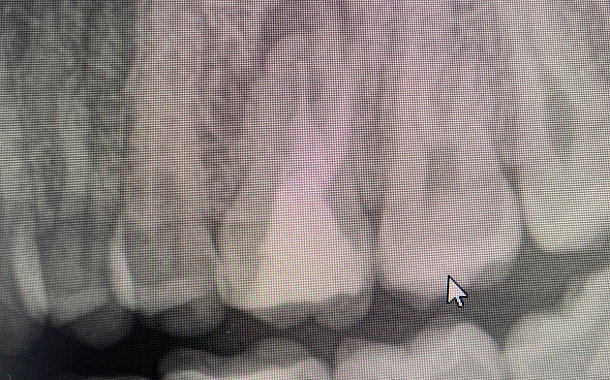

Применение Indiba после стоматологических процедур, таких как удаление зубов, костная пластика и имплантация, обеспечивает ряд значительных преимуществ:

- Исследование, опубликованное в Journal of Clinical Medicine (2020), показало, что применение Indiba после имплантации зубов ускоряет процесс остеоинтеграции на 30-40%.